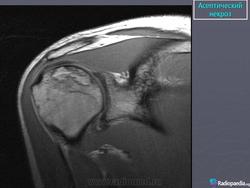

На ранних стадиях для выявления заболевания полезна магнитно-резонансная томография.

В начальной стадии АН рентгенологические изменения в костной ткани могут отсутствовать, поэтому для ранней диагностики патологических изменений необходимо применение МРТ. При наличии в анамнезе факторов риска развития АН (например, травмы), своевременно выявленные симптомы АН способствуют более раннему началу проведения лечебных мероприятий, направленных на устранение причин, и выбору правильной тактики лечения больных.